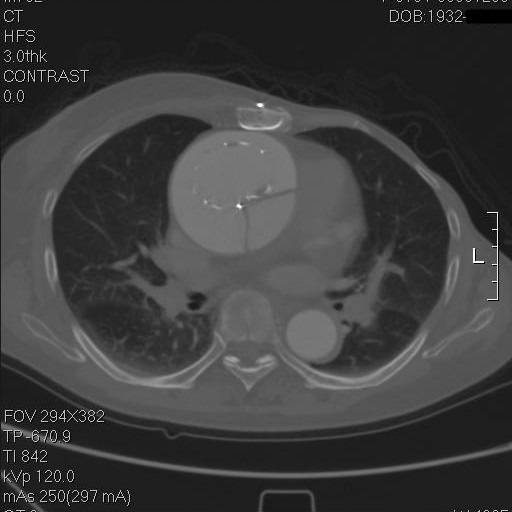

再往上,这个支架竟然是骑跨在真假腔之间的!

这个层面,支架终于完全在真腔内了,但假腔基本没有闭合。